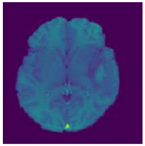

| Image | Ground Truth | Segmented Region | |

|---|---|---|---|

| Test Case1 | ![]() | ![]() | ![]() |

| Test Case2 | ![]() | ![]() | ![]() |